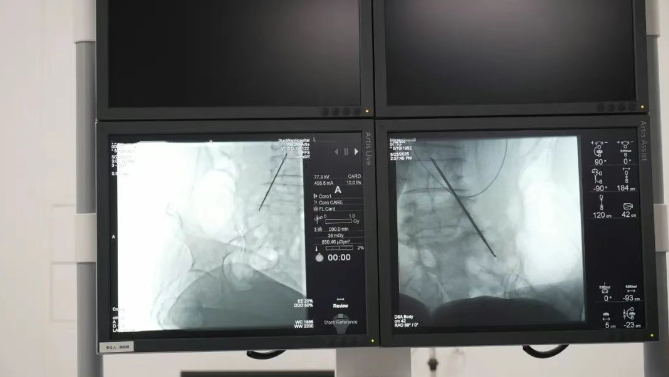

精準靶向,直擊疼痛根源鞘內(nèi)泵植入技術通過微創(chuàng)手段,將一枚微型鎮(zhèn)痛泵植入體內(nèi),經(jīng)導管精準連接至脊髓蛛網(wǎng)膜下腔(鞘內(nèi))。這一“生物鎮(zhèn)痛開關”可直接將鎮(zhèn)痛藥物輸送至中樞神經(jīng)系統(tǒng),相較傳統(tǒng)口服或靜脈給藥,所需藥量僅為1/300,卻能實現(xiàn)更高效、更精準的疼痛控制,從根源阻斷疼痛信號傳導,讓患者徹底擺脫疼痛困擾。